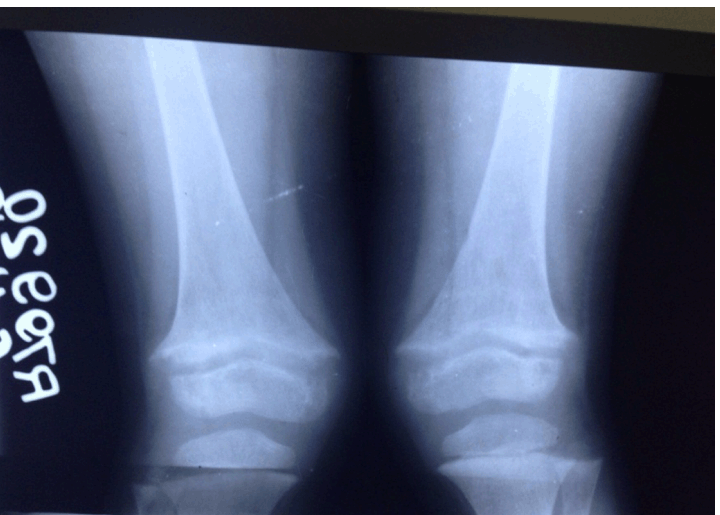

Since patient came to us after one month of injury, fracture was already in the stage of healing and was not mobile. Therefore, closed manipulation could not re-align the physis. Open reduction could further damage the physis in the growing child. So the child was managed conservatively on long leg cast and non-steroidal anti-inflammatory drugs (ibuprofen 100 mg b.d.) for two weeks. After pain decreased, patient was given intermittent skin traction for flexion deformity with range of motion exercises. Both slips healed within four months. Even these completely displaced slips remodeled very well. At six month of follow-up, all the slips were completely remodeled without obvious deformity. (Figure 3) Patient gained bilateral excellent range.

Figure 3: Anteroposterior X-rays after six months showing healed lesion.